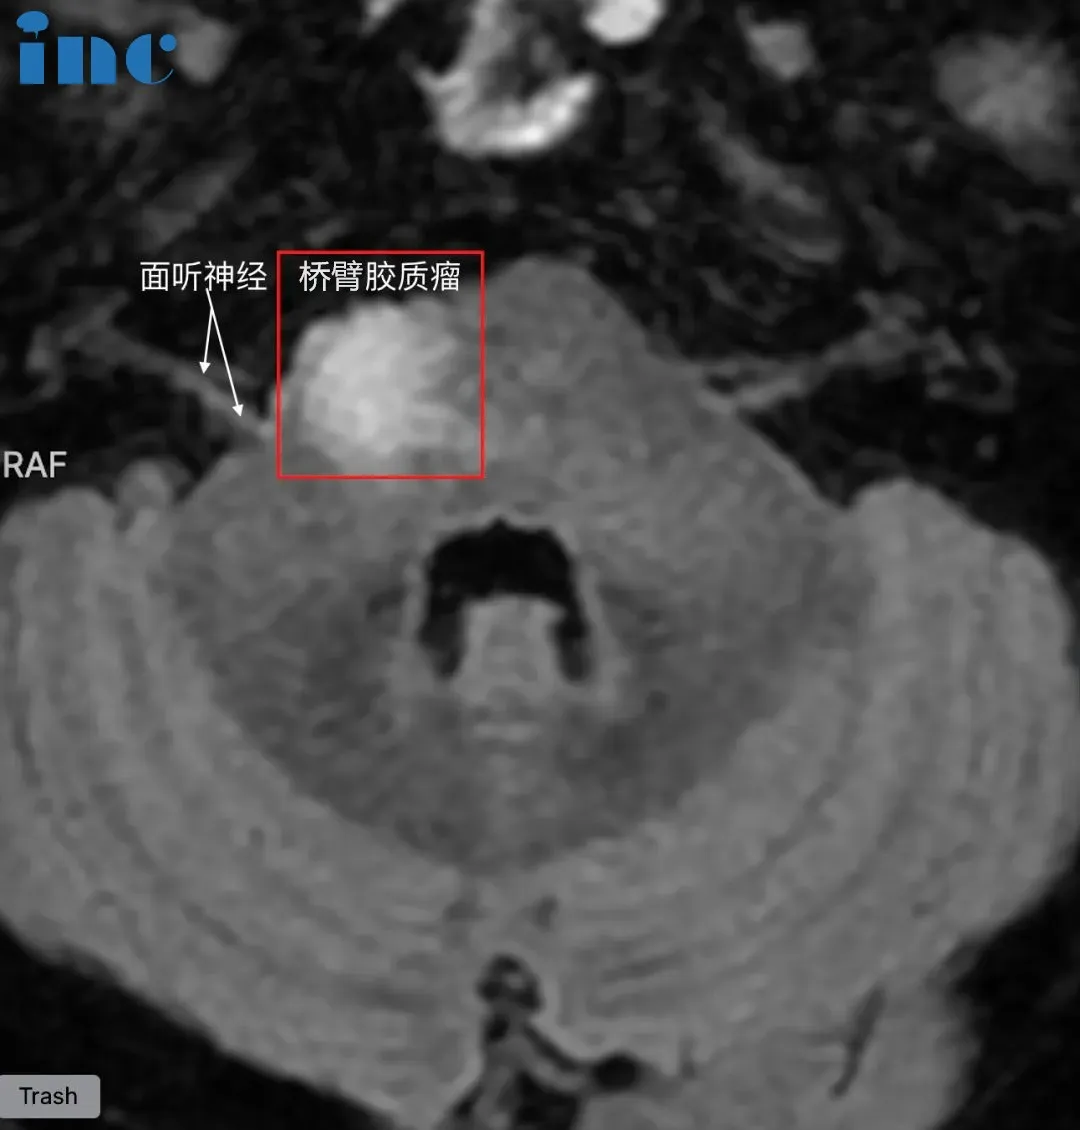

脑干-桥臂胶质瘤长大,三根重要神经包绕肿瘤

命运总会在人意气风发的时候,悄悄伸出脚把你绊倒。韩先生、30出头、高级工程师,正是家庭和事业蒸蒸日上的时候,这时却被胶质瘤病魔的触角缠住。短短不到一年,由初次诊断的疑似脱髓鞘病变,到病灶增大、怀疑胶质瘤。一边需要全身心投入高精尖工作之中,一边四处求医。“桥臂位置处于大脑深部,手术难度、风险都很大,不建议手术。”原本充满朝气的生活如今度日如年,心力憔悴的韩先生此时无路可走。

脑干桥臂位置,肿瘤还被面神经,滑车神经,听神经等重要神经包绕,手术难度之大不言而喻。巴教授是他们希望。2023年9月29日,中秋节当天,巴教授为韩先生成功手术。